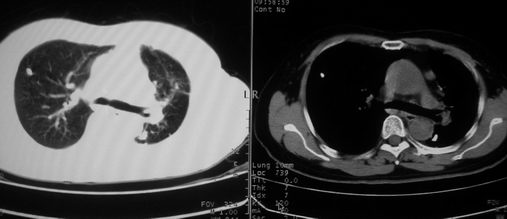

以下是引用李衡钧在2008-7-24 14:24:00的发言:[br]左侧胸廓变小,左肺上叶见大面积致密阴影,其内有空洞及不规则钙化。上纵隔略向左移位,上肺胸膜增厚。左肺门及纵隔淋巴结增大。右肺见散在的致密结节影。[br]印象:继发性肺结核。